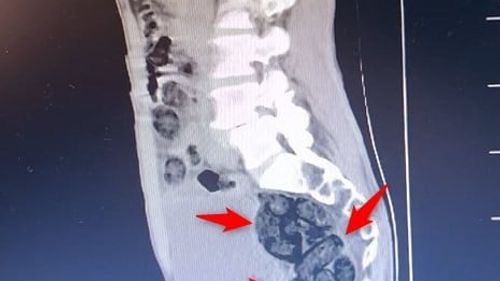

Batman'da durdurulan otobüsteki yabancı yolcunun midesinden 64 parça, toplam 472 gram metamfetamin çıkarıldı; şahıs tutuklandı.

Batman'da Yabancı Yolcunun Midesinden 64 Parça Uyuşturucu Çıktı Batman İl Emniyet Müdürlüğü Narkotik Suçlarla Mücadele Şube Müdürlüğü ekipleri, Batman Cumhuriyet Başsavcılığı koordinesinde yürütülen çalışma kapsamında Batman girişinde durdurulan bir otobüste arama yaptı. Operasyon ve Bulgular Aramada durumundan şüphelenilen yabancı uyruklu…